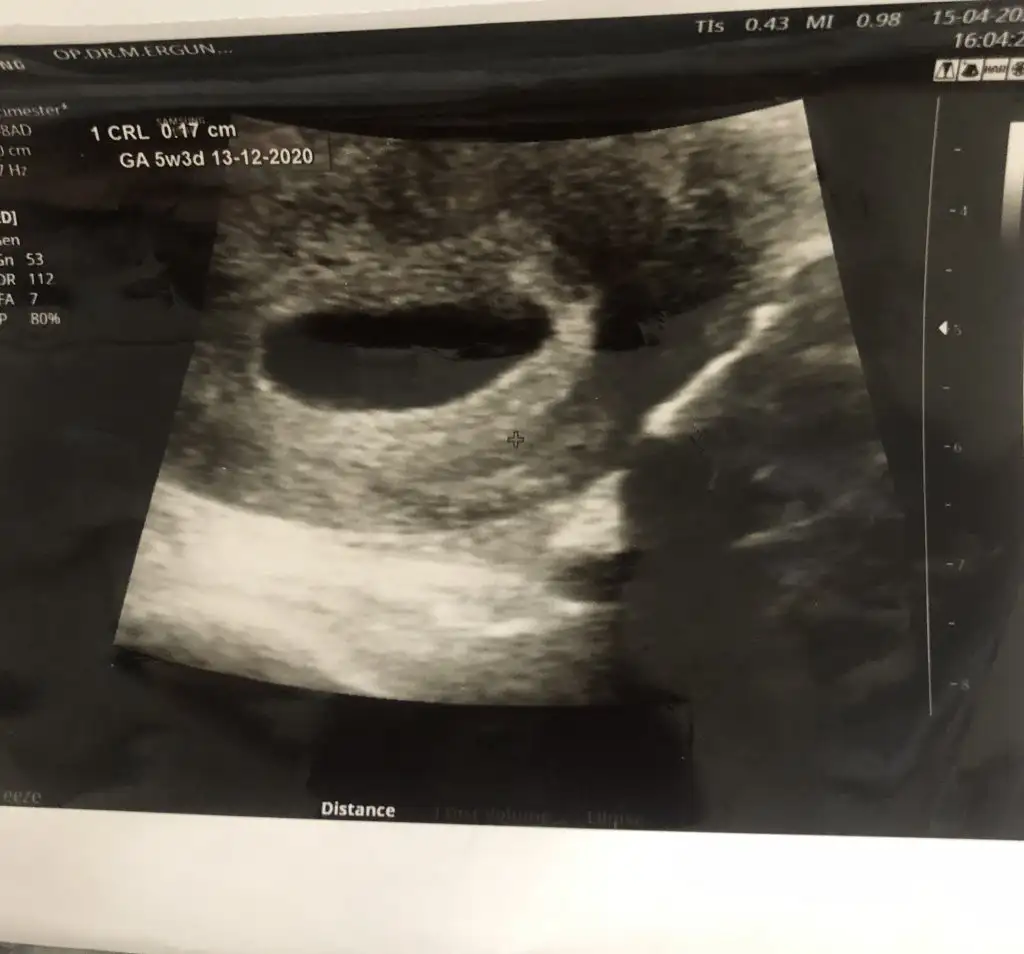

5+3 haftadayım burda

bana ilk gittiğimde kesen ne kadar büyük dedi zaten ilk 4+3 kan değerinde çok yüksekti 795221 çıktı ikiz olmasından şüphelendiler bir başka sayfada erkek bebeklerde değer yüksek çıkar dediler bakalım sonuç ne çıkacak5+3 haftadayım burda

Burda 5+3 haftalık3. Çocuklar fazla merak konusu oldu bizdehayırlısı bakalim bende çok araştırıyorum nedense